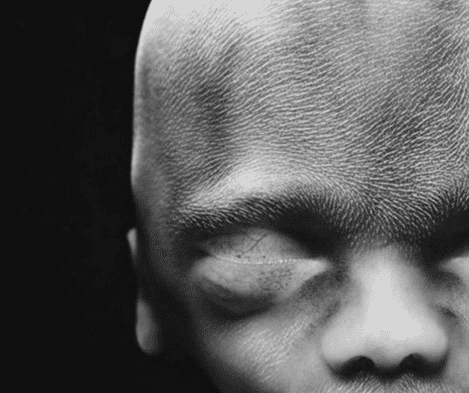

13. 10 semaines de développement

14. À 10 semaine, le foetus commence à utiliser ses mains